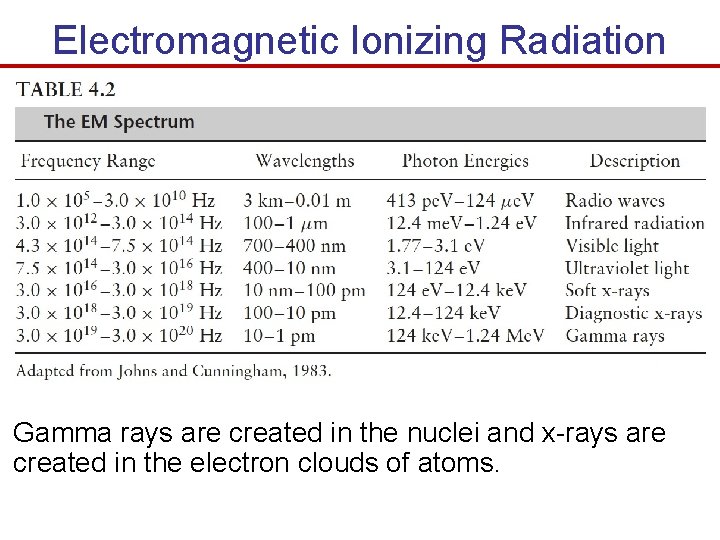

Electromagnetic Ionizing Radiation Gamma rays are created in the nuclei and x-rays are created in the electron clouds of atoms.